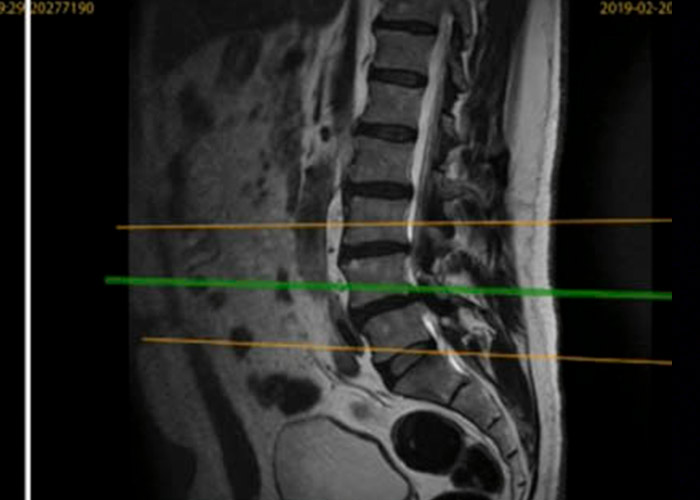

Preoperatorio

Caso de recidiva de Hernia discal en Madrid, operada previamente mediante cirugía abierta

preoperacion-recidiva-hernia-discal-en-madrid